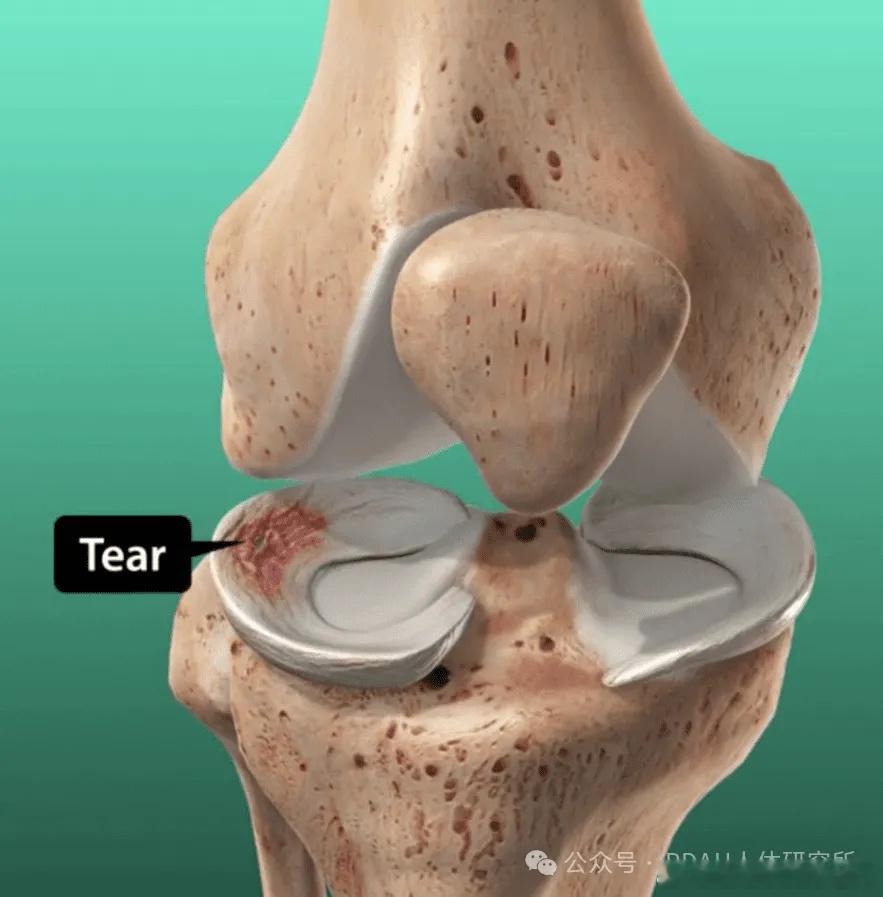

膝关节损伤 【半月板损伤】半月板伤了,手术or保守,该怎么康复?今天就来聊一聊——【半月板的功能】✅稳定膝关节、传递应力、协助润滑关节——半月板由2个纤维软骨板构成呈"C"字型,外缘厚,内缘薄 图1,紧密附着在胫骨平台中部的髁间结节处 图2。——胫股关节是一个完全不吻合曲面,通过膝关节的应力集中在很小的面积上,有了半月板,关节接触面积增大,应力就不会过于集中,关节稳定性也会增强。因此在切除半月板时,应尽量地保存未遭损伤的半月板,从而最大可能地保留半月板的功能。【半月板损伤机制】⚠️扭转——当膝关节处于屈曲位、而胫骨固定时股骨下端由于外力骤然过度内旋、伸直,可导致内侧半月板撕裂,或者股骨下端骤然外旋、伸直外侧半月板也可发生破裂; ⚠️压力——起跳或高处落下时,如果人体的缓冲技术不到位/膝关节压力过大也可能造成半月板撕裂;⚠️膝关节急速扭转,又受到横向外力——也易造成半月板撕裂同时可能并发膝关节前交叉韧带撕裂或断裂。而由于半月板的运动机制,内侧半月板破裂的机会比外侧半月板多7-10倍。【保守治疗】①半月板是在血供丰富区的撕裂(外侧血供比内侧丰富);②撕裂不要超过2cm长度;③膝关节要带夹板限制活动6周;④根据半月板缝合的情况进行康复;⑤急性伤。如果是处于急性损伤,就需要遵循RICE原则:制动、冰敷、加压、抬高。半月板康复健闻登顶计划